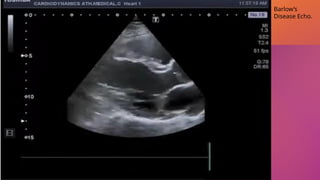

Barlow disease: is an infiltrative disease characterized by

excessive myxomatous tissue associated with

mucopolysaccharide accumulation that can affect one or both

leaflets, and chordae.

In Barlow disease, there is thickening of the leaflets leading to

redundant valvular tissue and frequently elongated or ruptured

chordae.

Patients with Barlow disease are usually diagnosed in young

adulthood and typically present with bileaflet and

multisegmental prolapse with or without flail scallops

Video Coutresy of Cardiodynamic Athens YouTube cha

nnel

Barlow’s

Disease Echo.